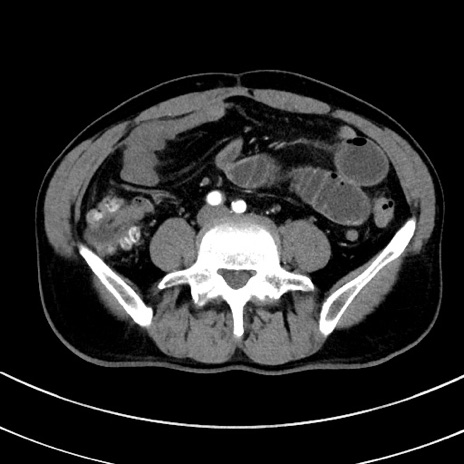

症例8(横断像)

【症例】 60歳代男性

【主訴】 黒色吐物

【現病歴】 4日前から嘔気自覚、2日前の朝食後にも嘔気あり、自分で手で嘔吐反射起こし嘔吐したところ血が混ざっていたため受診。

【既往歴】 5年前汎発性腹膜炎を伴う急性虫垂炎で手術、高血圧、前立腺肥大症、高脂血症

【身体所見】 腹部正中に手術癩痕あり 腹部平坦・軟圧痛なし膨満感あり

【データ】WBC 8400、CRP 4.54